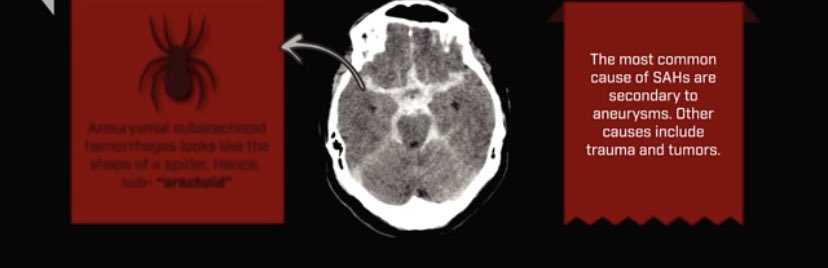

▫️Subarachinoid hemorrhage🩸🧠

✳️Blood in cisterns and fissures that resemble spider 🕷 shape